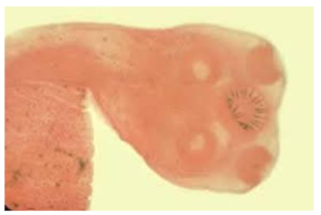

Taenia solium (pork tapeworm) scolex

knowt flashcard image